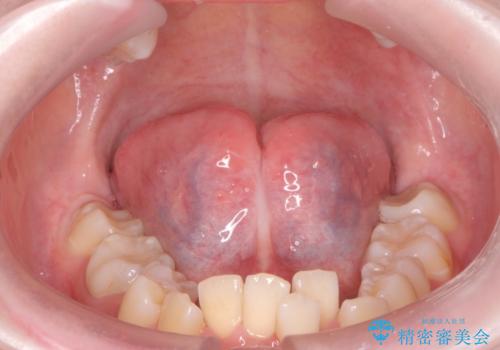

[ 舌小帯の形成術 ] ラ行の発音を改善したい

担当医 大元洋佑